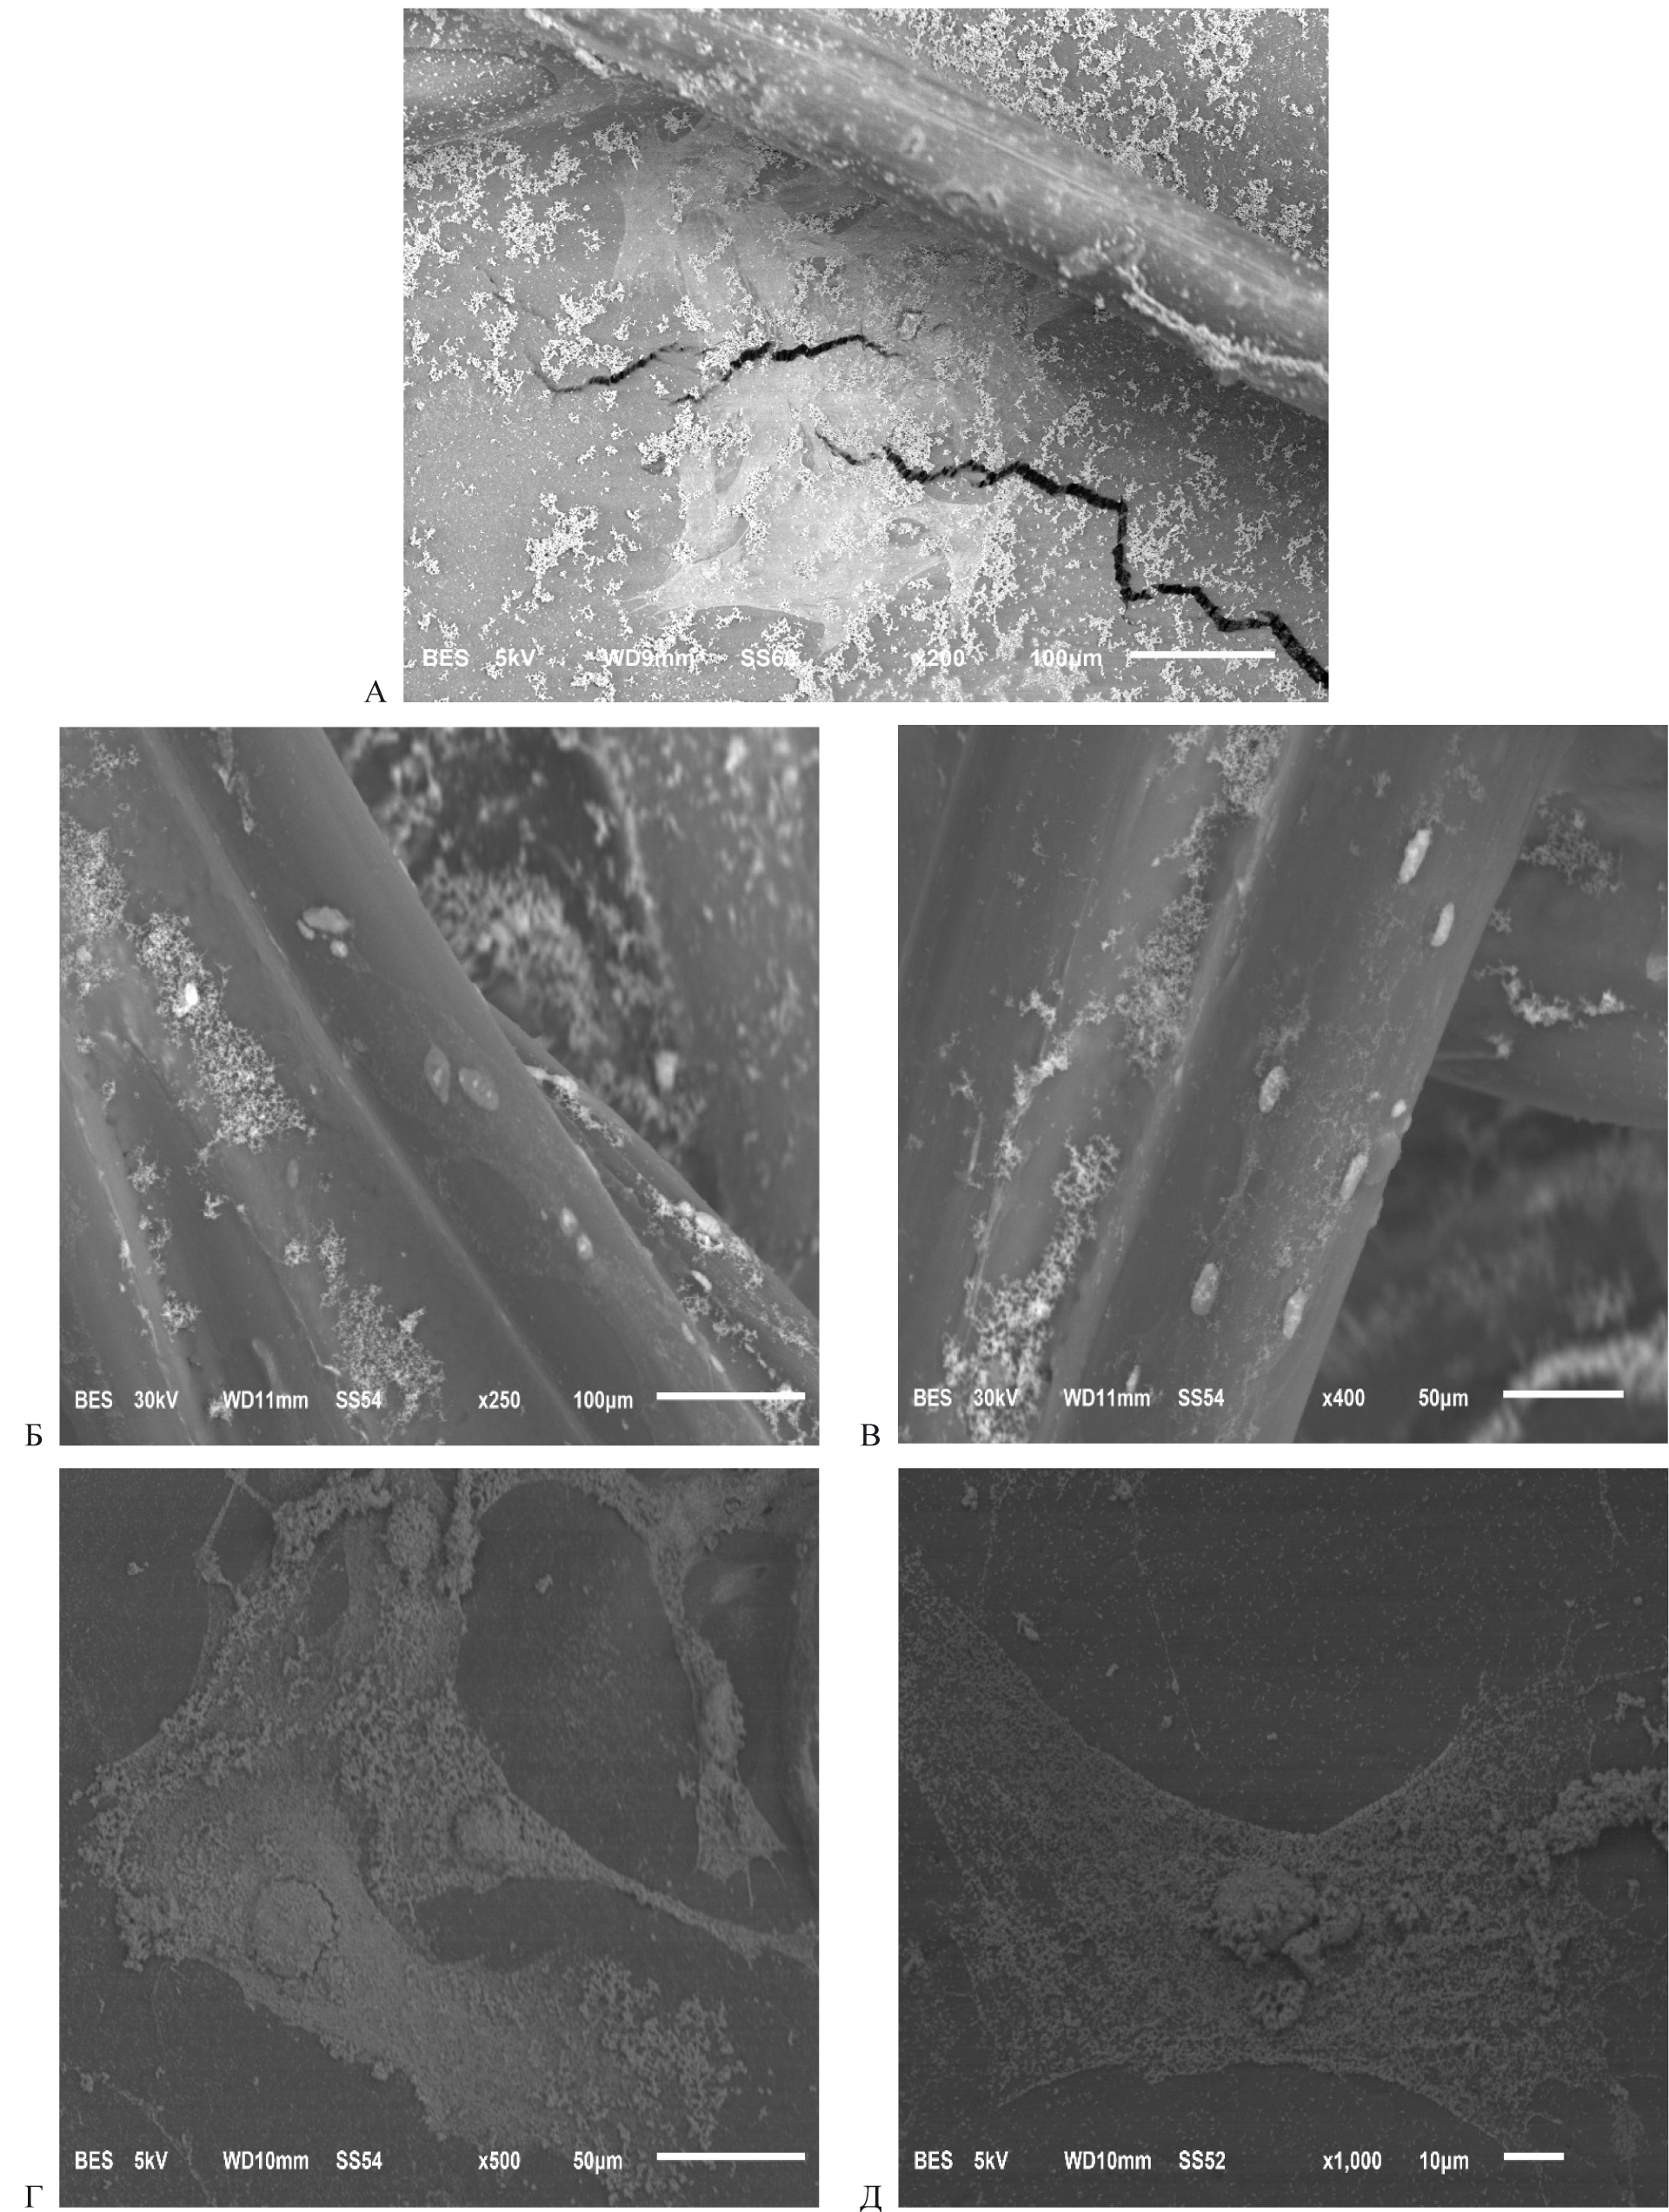

В результате полученных исследований было выявлено, что после культивирования дермальных аутофибробластов в течение 5 суток происходит их прикрепление к нитям эндопротеза. В группе с использованием герниопротеза «Унифлекс стандартный» на нитях синтетического материала визуализировались единичные клетки округлой или овальной формы. Большая часть клеток прикреплялась ко дну флакона, приобретая характерную распластанную форму с большим количеством отростков (рис. А).

В группе «Унифлекс стандартный» с последующей обработкой поликапролактоном вокруг нитей протеза визуализировались группы фибробластов. Большая часть клеток имели распластанную или вытянутую форму, что свидетельствует о прочности прикрепления к материалу (рис. Б, Д). Важно, что клеточный рост определялся как вокруг мест переплетения, так и между прямыми нитями.

Рис. Микрофотография при электронной микроскопии поверхности сетчатого эндопротеза «Унифлекс стандартный». СЭМ: А – без предварительной обработки протеза (ув. ×200 × 10-6); Б – с обработкой поликапролактоном (ув. ×250 × 10-6); В – с обработкой поликапролактон + низкотемпературная плазма (ув. . ×400 × 10-6); Г – с обработкой поликапролактоном (ув. ×500 × 10-6; Д – с обработкой поликапролактон + низкотемпературная плазма (ув. ×400 × 10-6)

В группе «Унифлекс стандартный» с обработкой поликапролактон + низкотемпературная плазма также определялось прикрепление фибробластов к герниопротезу. При этом клетки преимущественно располагались поодиночке, имели округлую форму и локализовались только на прямых нитях, а в местах плетения отсутствовали (рис. В, Г). С учетом достаточно упорядоченного клеточного «рисунка» можно предположить, что клетки плотно фиксировались в местах насечек, полученных в результате обработки низкотемпературной плазмой. Такой способ обработки синтетического материала подходит для исключительно стерильных условий, так как данные насечки могут служить местом локализации не только клеток соединительной ткани, но и бактерий.